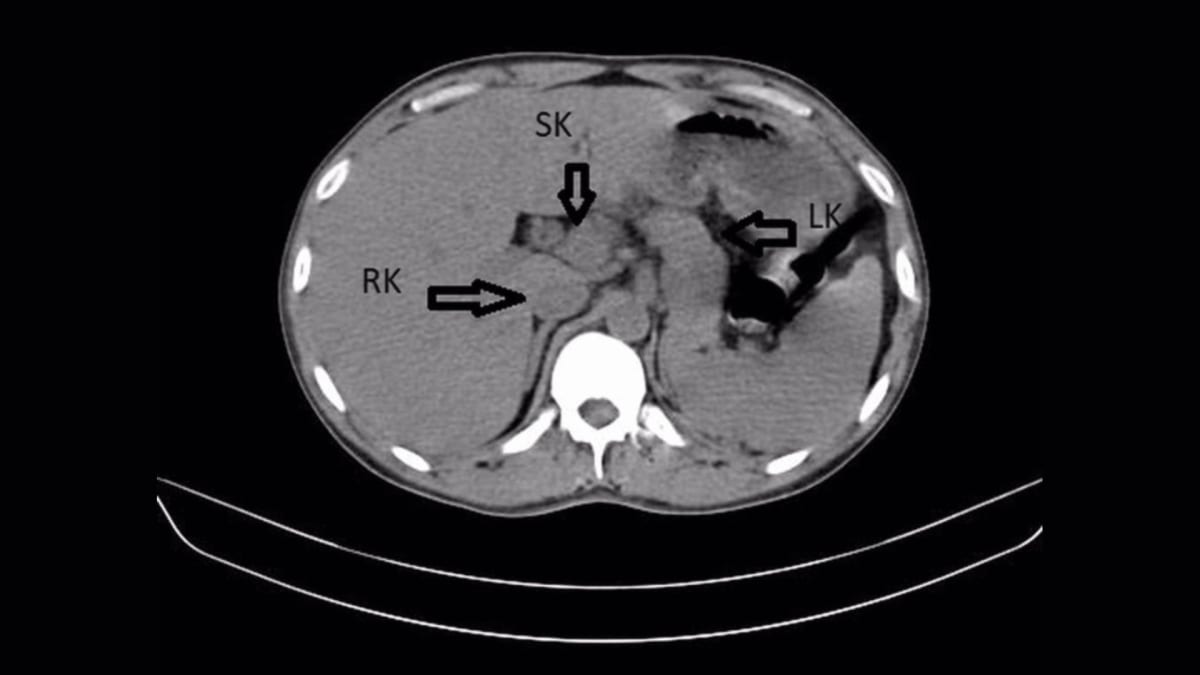

But when doctors performed an ultrasound and CT scan of his abdomen, they spotted something extraordinary. The man had three fully formed kidneys instead of the usual two.

The extra kidney, called a supernumerary kidney, was fused to his right kidney in a horseshoe shape. It had been there since before he was born, quietly doing its job alongside his other two kidneys without causing any noticeable problems.

The fused horseshoe appearance made this case even more unusual. Only five similar cases exist in scientific literature.

The scans also revealed the real source of the man's pain: mineral crystal buildup in his kidneys and left ureter, the tube connecting his kidney to his bladder. These hard deposits, combined with bacterial infection, had caused his severe symptoms.